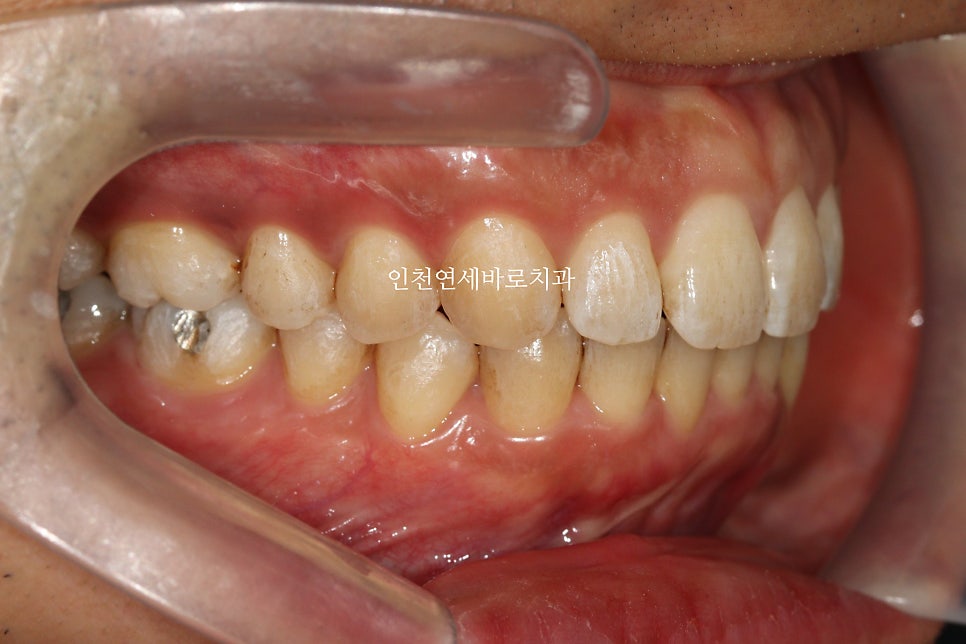

앞니가 뻗쳐있고, 아래치아가 안보이고

덧니가 심해서 내원한 환자분입니다

치료 전과 후의 비교입니다.

교합도 양호하게 마무리.

악궁의 확장을 통한 앞니의 후방이동도 최대한 이루어냈습니다.